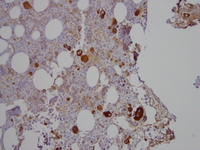

Factor VIIIvw immunohistochemistry stain

Factor VIIIvw immunohistochemistry stain highlights atypical megakaryocytes showing range in size with small mononuclear forms.

Refractory-cytopenia-of-childhood-GATA2-deficiency-related-Factor-VIIIvw-immunohistochemistry-stain